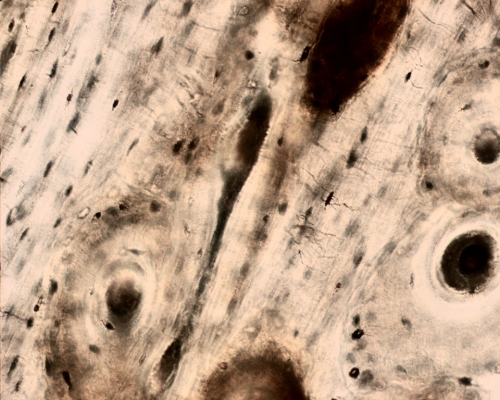

Ground section of bone